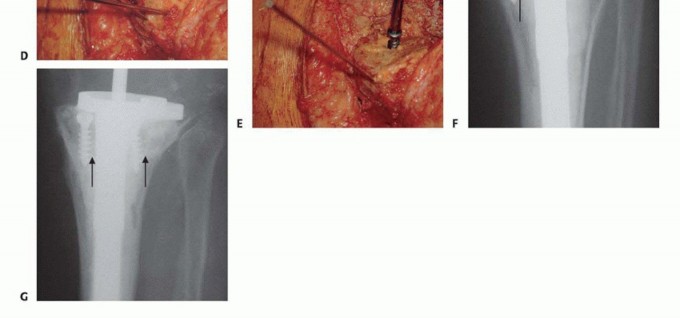

A fresh frozen femoral head or distal femoral allograft is selected. The host bone is prepared by resecting the remaining structurally incompetent bone to a flat, bleeding surface. The allograft is then meticulously shaped to match the host defect perfectly. The "seven up" technique is frequently used, where the graft is shaped into a figure seven to sit on the prepared host ledge while allowing the intramedullary stem to pass centrally.

The structural allograft is temporarily secured to the host tibia using Kirschner wires. The allograft host construct is then reamed as a single unit to accept the diaphyseal stem. Definitive fixation of the structural allograft to the host bone is typically achieved with interfragmentary lag screws or by the press fit interference of the diaphyseal stem passing through both the graft and the host diaphysis.

Cementless, fluted, tapered stems are widely favored as they provide excellent rotational stability and immediate rigid fixation in the diaphysis. The metaphyseal portion of the implant, resting on the bone graft, is typically cemented. Care must be taken to prevent cement extrusion between the structural allograft and the host bone interface, as this will mechanically block biological incorporation and lead to graft nonunion. Offset stems may be required to accommodate the mismatch between the center of the diaphyseal canal and the center of the tibial plateau, ensuring optimal coverage of the reconstructed metaphysis.

Structural allografts are particularly susceptible to specific failure modes, including nonunion at the host graft interface, late graft resorption, and structural fracture of the allograft. Because bulk allografts are avascular and incorporate slowly via creeping substitution, they remain mechanically vulnerable for years postoperatively. Infection is another catastrophic complication, as the massive avascular graft serves as a perfect nidus for biofilm formation.